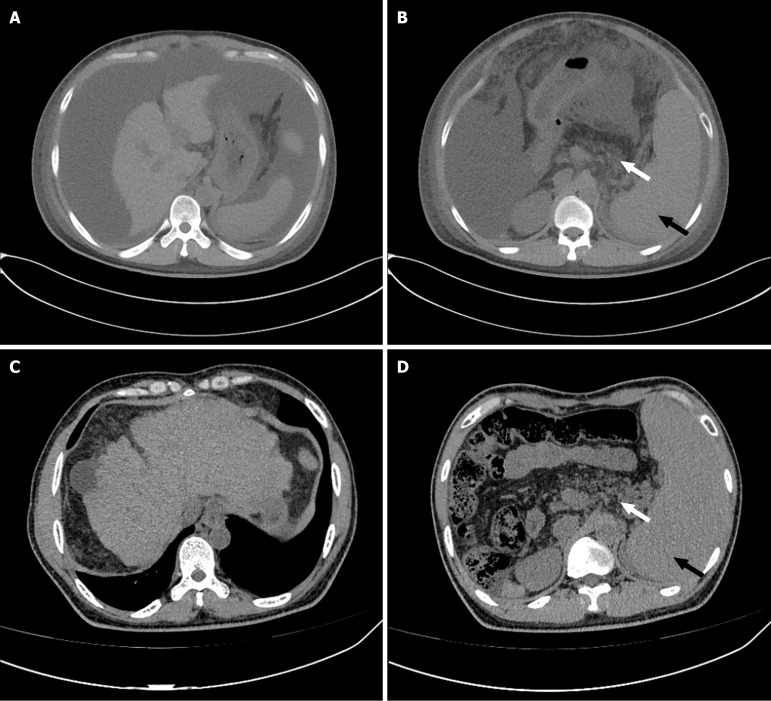

Case summary: A 36-year-old male patient presented with massive ascites. Laboratory tests revealed pancytopenia and a serum-ascites albumin gradient greater than 1.1 g/dL. An abdominal computed tomography scan demonstrated cirrhosis, splenomegaly, pancreatic fat infiltration, and a substantial accumulation of peritoneal fluid. Gastroscopy identified esophageal varices. Liver stiffness measurement indicated a value of 32.7 kPa. Based on the results of auxiliary examinations, common causes of cirrhosis were excluded, and a mutation in the Shwachman-Bodian-Diamond syndrome gene was ultimately identified through whole-exome sequencing. The patient was diagnosed with cirrhosis secondary to SDS. Following the correction of hypoalbuminemia and administration of diuretics, the patient's ascites resolved.